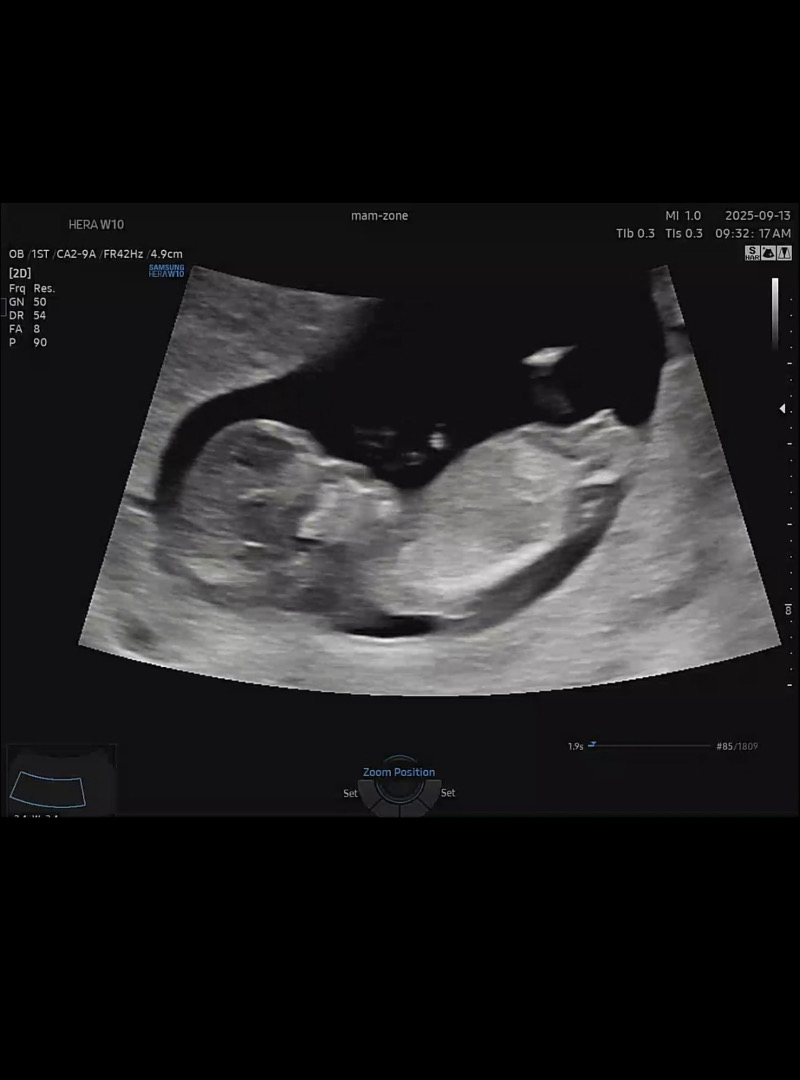

각도법쫌봐주세요~

12주입니다 아들일까요 딸일까요?